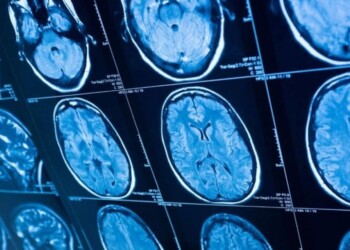

Qué es la Corea de Huntington, de la que hoy se conmemora el Día Mundial

Cada 13 de noviembre se conmemora el Día Internacional de la Enfermedad de Huntington, una afección que provoca la degradación ...